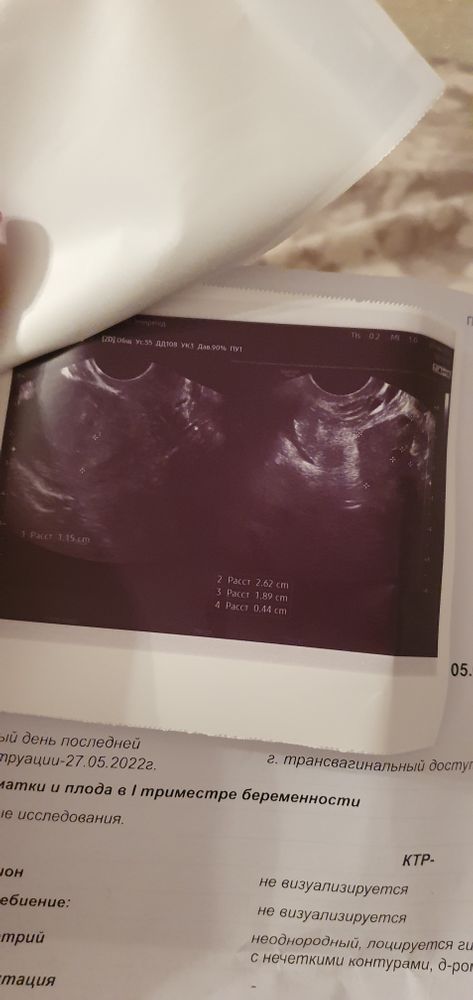

Цикл ровный, 28 дней, овуляцию всегда чувствую, и в день о был па. Теперь 22 сделала тест была еле видная полоска, переделывала несколько раз в несколько дней и вот ято по тестам. Теперь сегодня была на узи, а по узи ято то не радостно :(

Вопрос: расшифруйте узи :) конкретно что значит гипоэхогенное и анэхогенное обр-е